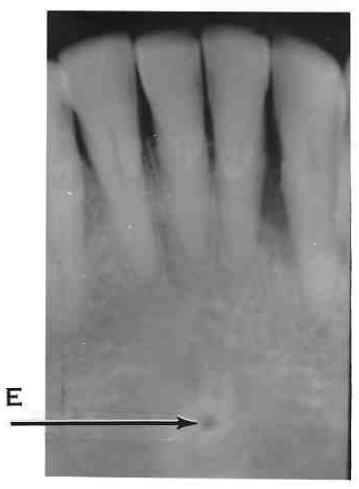

11. Which option is indicated by arrow E?

13. Arrow E showing which anatomical structure?

14. What is showing by E?